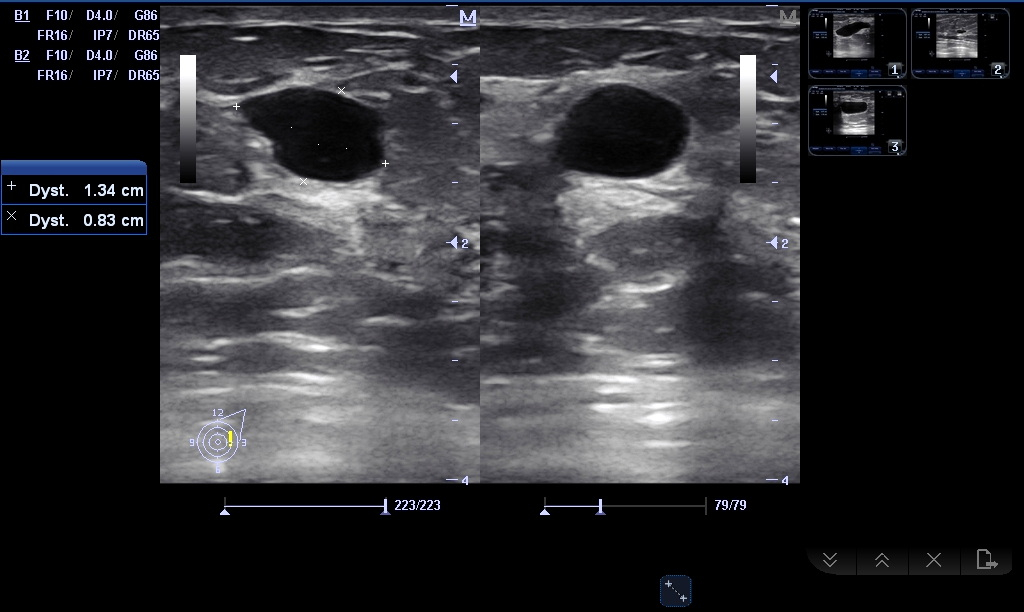

Nowe przypadki USG Przemyśl Poniżej znajdą Państwo zdjęcia najnowszych wykrytych w naszym Gabinecie przypadków patologii Angiomyolipoma (AML) nerki Kamica pęcherzyka żółciowego Naczyniak wątroby Kamica pęcherzyka, pogrubienie ściany Podwójny UKM nerki Naczyniak wątroby Przewlekłe odmiedniczkowe zapalenie nerek Rak sutka Rak sutka Śledziona dodatkowa Torbiel jajnika Torbiel piersi Torbiel piersi